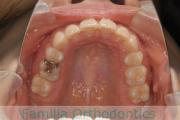

No.23V-061

- 主な症状:

- 叢生

- その他の症状:

- 上下顎前突

- 年齢:

- 23歳

- 性別:

- 女性

- 抜歯部位

- 上:

- 44

- 下:

- 主な使用装置:

- FEA 022

- 治療にかかった費用:

- 88万円

でこぼこを綺麗に並べたいということで来院されました。上下左右から小臼歯を抜歯して、マルチブラケット法を2年半、30回程度通院していただいて行いました。

かなり強い叢生(でこぼこ、凹凸、ガタガタ)のため、保定をしっかりしないと後戻りのリスクが高いケースといえます。

- ≫治療前

上顎

下顎